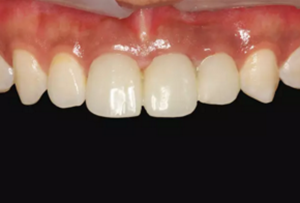

圖23 最終修復(fù)后即刻口內(nèi)像

圖25 最終修復(fù)后復(fù)查口內(nèi)像

(5)復(fù)查。種植體周圍骨水平穩(wěn)定,齦乳頭及齦高點位置穩(wěn)定,齦緣 曲線形態(tài)理想,唇側(cè)軟硬輪廓良好,功能滿意,修復(fù)效果符合預(yù)期。

本病例在觀察期內(nèi),種植修復(fù)獲得了良好的軟硬組織美學(xué)效果和穩(wěn)定 性?;颊邔χ委熜Ч麧M意。